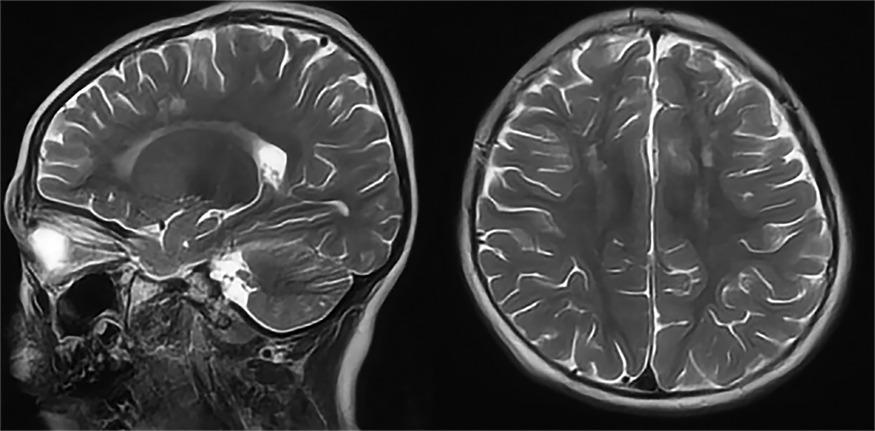

Диагностический комплекс анализирует метаболические процессы в тканях мозга, отслеживая утилизацию глюкозы с помощью фтордезоксиглюкозной позитронно-эмиссионной томографии. Система сопоставляет полученные изображения с обширным архивом медицинских данных и выявляет характерные метаболические сигнатуры различных патологических процессов.

StateViewer успешно дифференцирует патологические изменения, характерные для различных форм деменции. Технология распознает метаболические нарушения в височно-теменных зонах при болезни Альцгеймера, идентифицирует дисфункцию в областях внимания и моторного контроля при деменции с тельцами Леви, а также выявляет изменения в лобно-височных регионах, ответственных за речевые и поведенческие функции.